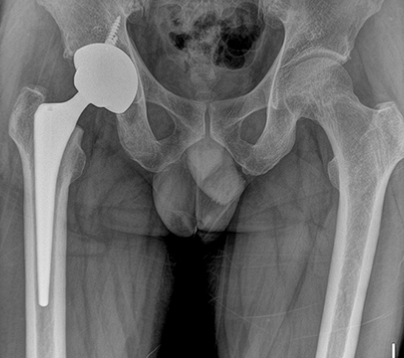

두번쨰로는 대퇴골두에만 인공뼈를 삽입하여 치환시키는 방법과 세번째로는 관절 부분 전체를 인공관절로 바꿔주는 방법이 있습니다. 이 경우에는 심하게 괴사가 된 경우에 사용하는 방법으로 합병증이 적고 기능개선이 우수하다고 알려져 있습니다.

보통 인공관절 수술방법으로 많이들 시행합니다. 병원마다 금액이 전부 다르기 때문에 정확한 금액을 알려드릴수는 없으나, 보통 180만원 부터 250만원까지 다양하기 때문에 꼭 전문의와 상담하여 수술방법과 수술비용에 대해 상담하시길 당부드립니다.